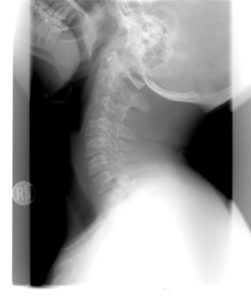

Ročně nastanou tisíce dopravních nehod se zraněním. Jaké jsou nejčastější zranění při autonehodě? Obvykle se jedná o pohmožděniny a zlomeniny. Velmi často nastane také poranění krční páteře při autonehodě. Tzv. opěrkový syndrom (whiplash trauma) může působit jako lehké zranění, bohužel se však v praxi setkáváme s tím, že vzniknou trvalé následky po poranění krční páteře. Tyto trvalé následky lze obvykle odškodnit jako ztížení společenského uplatnění.

Tip od právníka: I když nebyla nezbytná hospitalizace, doporučujeme co nejdříve navštívit lékaře. Některá zranění, například již zmiňované poškození krční páteře, se mohou projevit až po několika hodinách po nehodě.